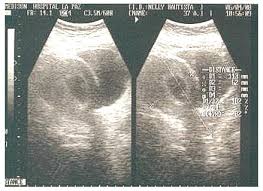

La ecografía abdominal se considera a menudo como la primera opción de imagen en mujeres embarazadas con sospecha de apendicitis, debido a su disponibilidad, seguridad y falta de exposición a la radiación. Sin embargo, es importante tener en cuenta que la visualización del apéndice en la ecografía puede ser difícil, especialmente durante el embarazo, debido a la posición alterada del órgano y a la presencia de gas intestinal que puede interferir con la imagen. Por lo tanto, la no visualización del apéndice en la ecografía no descarta por completo la posibilidad de apendicitis y puede requerir la realización de otras pruebas de imagen.